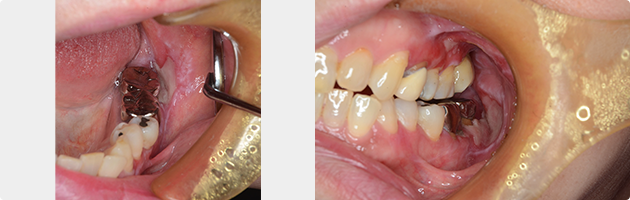

扁平苔癬

慢性の炎症性角化病変。明らかな原因は不明です。細菌やストレス、金属アレルギーなどが原因として考えられます。原因、誘発要因を除去し、局所に痛みがあれば消炎処置を行いました。